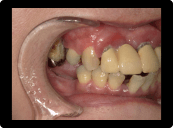

歯周病の治療例

奥歯の重度歯周病は保存困難のため抜歯してインプラント治療。残す歯は歯周病中等度であったため、歯周基本治療歯周外科治療を含めて行い、歯茎からの出血などはなくなった。

BEFORE

AFTER

症例概要

年代・性別

50代 女性

主訴

全体の歯茎から出血する、奥歯が揺れて噛めないことを主訴に来院されました。

治療内容

全顎歯周外科治療(保険治療)+奥歯インプラント治療4本

治療期間

6ヶ月

治療のリスク

歯肉退縮のリスクがあります

治療費用

約160万円